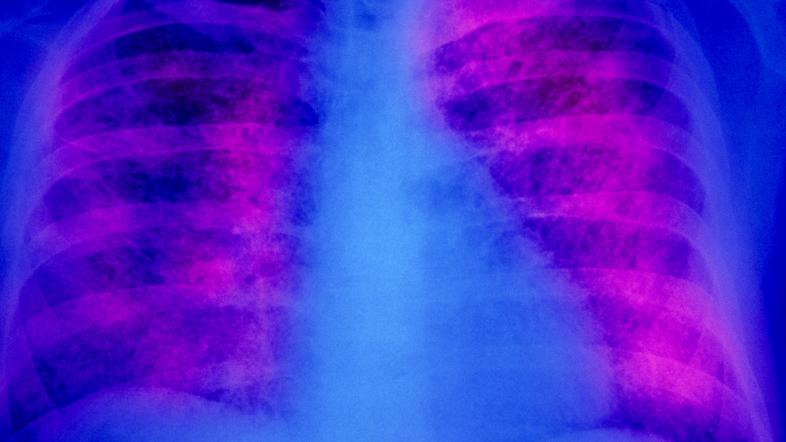

Tuberkuloza Profimedia Tuberkuloza

WHO opozarja: V Evropi in osrednji Aziji vse več primerov tuberkuloze med otroki

Mlajši od 15 let so leta 2023 predstavljali 4,3 odstotka novoodkritih ali ponovljenih primerov tuberkuloze v evropski regiji, kot jo definira Svetovna zdravstvena organizacija (WHO), kar glede na danes objavljeno poročilo o razširjenosti tuberkuloze pomeni zaskrbljujoč porast.

WHO in Evropski center za preprečevanje in obvladovanje bolezni (ECDC) v danes objavljenem poročilu z naslovom Nadzor in spremljanje tuberkuloze v Evropi ugotavljata, da je bilo v evropski regiji WHO v letu 2023 prijavljenih več kot 172.000 novih in ponovljenih primerov te nalezljive bolezni.

Ugotovitve poročila glede na skupno izjavo WHO in ECDC kažejo, da se tuberkuloza v evropski regiji WHO še vedno širi. Obe organizaciji opozarjata, da so potrebni "takojšnji javnozdravstveni ukrepi za nadzor in zmanjšanje naraščajočega bremena tuberkuloze".

Poročilo, objavljeno ob današnjem svetovnem dnevu tuberkuloze, po navedbah avtorjev kaže tudi na zaskrbljujoč porast primerov tuberkuloze med otroki. Med mlajšimi od 15 let so namreč leta 2023 v evropski regiji WHO zabeležili desetodstoten porast zabeleženih primerov te bolezni.